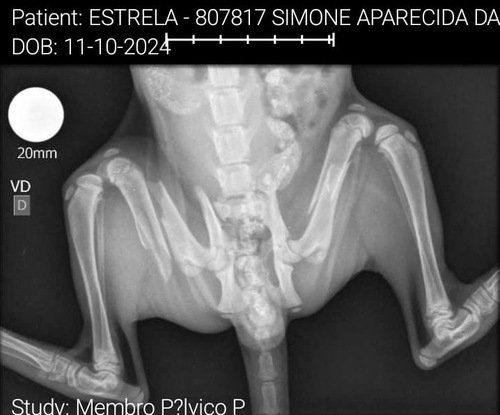

Ontem resgatamos a gatinha estrela de apenas 2 meses após atropelamento com fuga, ela quebrou os 2 fêmur da patinha traseira. Ela mia de dor o tempo todo.

Não temos como arcar com a cirurgia, sem ajuda de vocês. Conseguimos fazer os exames de RX e ultrassom para preparar ela para a cirurgia. Porém, não temos mais como fazer os demais exames e a cirurgia.

Levamos ela no hospital público, porém eles não fazem a cirurgia por ser ainda muito pequena, a prefeitura não manda placas tão pequenas. Não Temos condições no momento de fazer a cirurgia das patinhas.